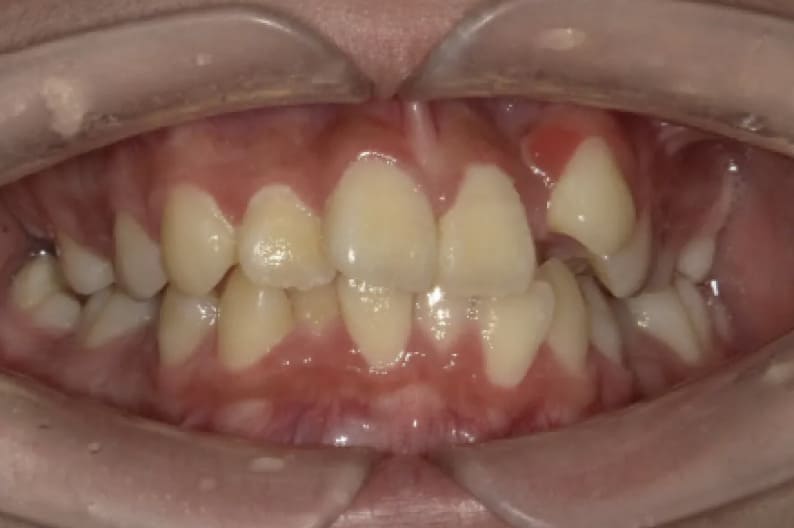

| After | ![]() |

| 性別 | 女性 |

| 年齢 | 10代 |

| 治療費用 | 902,000円 |

| 治療期間 | 2年11ヶ月 |

| 治療内容 | マウスピース矯正 |

| リスク 副作用 |

矯正治療の一般的なリスクといたしましては、治療中のお痛み・歯根吸収・歯肉退縮・治療後の後戻りなどが生じる可能性があります。矯正治療は始めると、元の状態に戻すのが難しいことがあります。 |